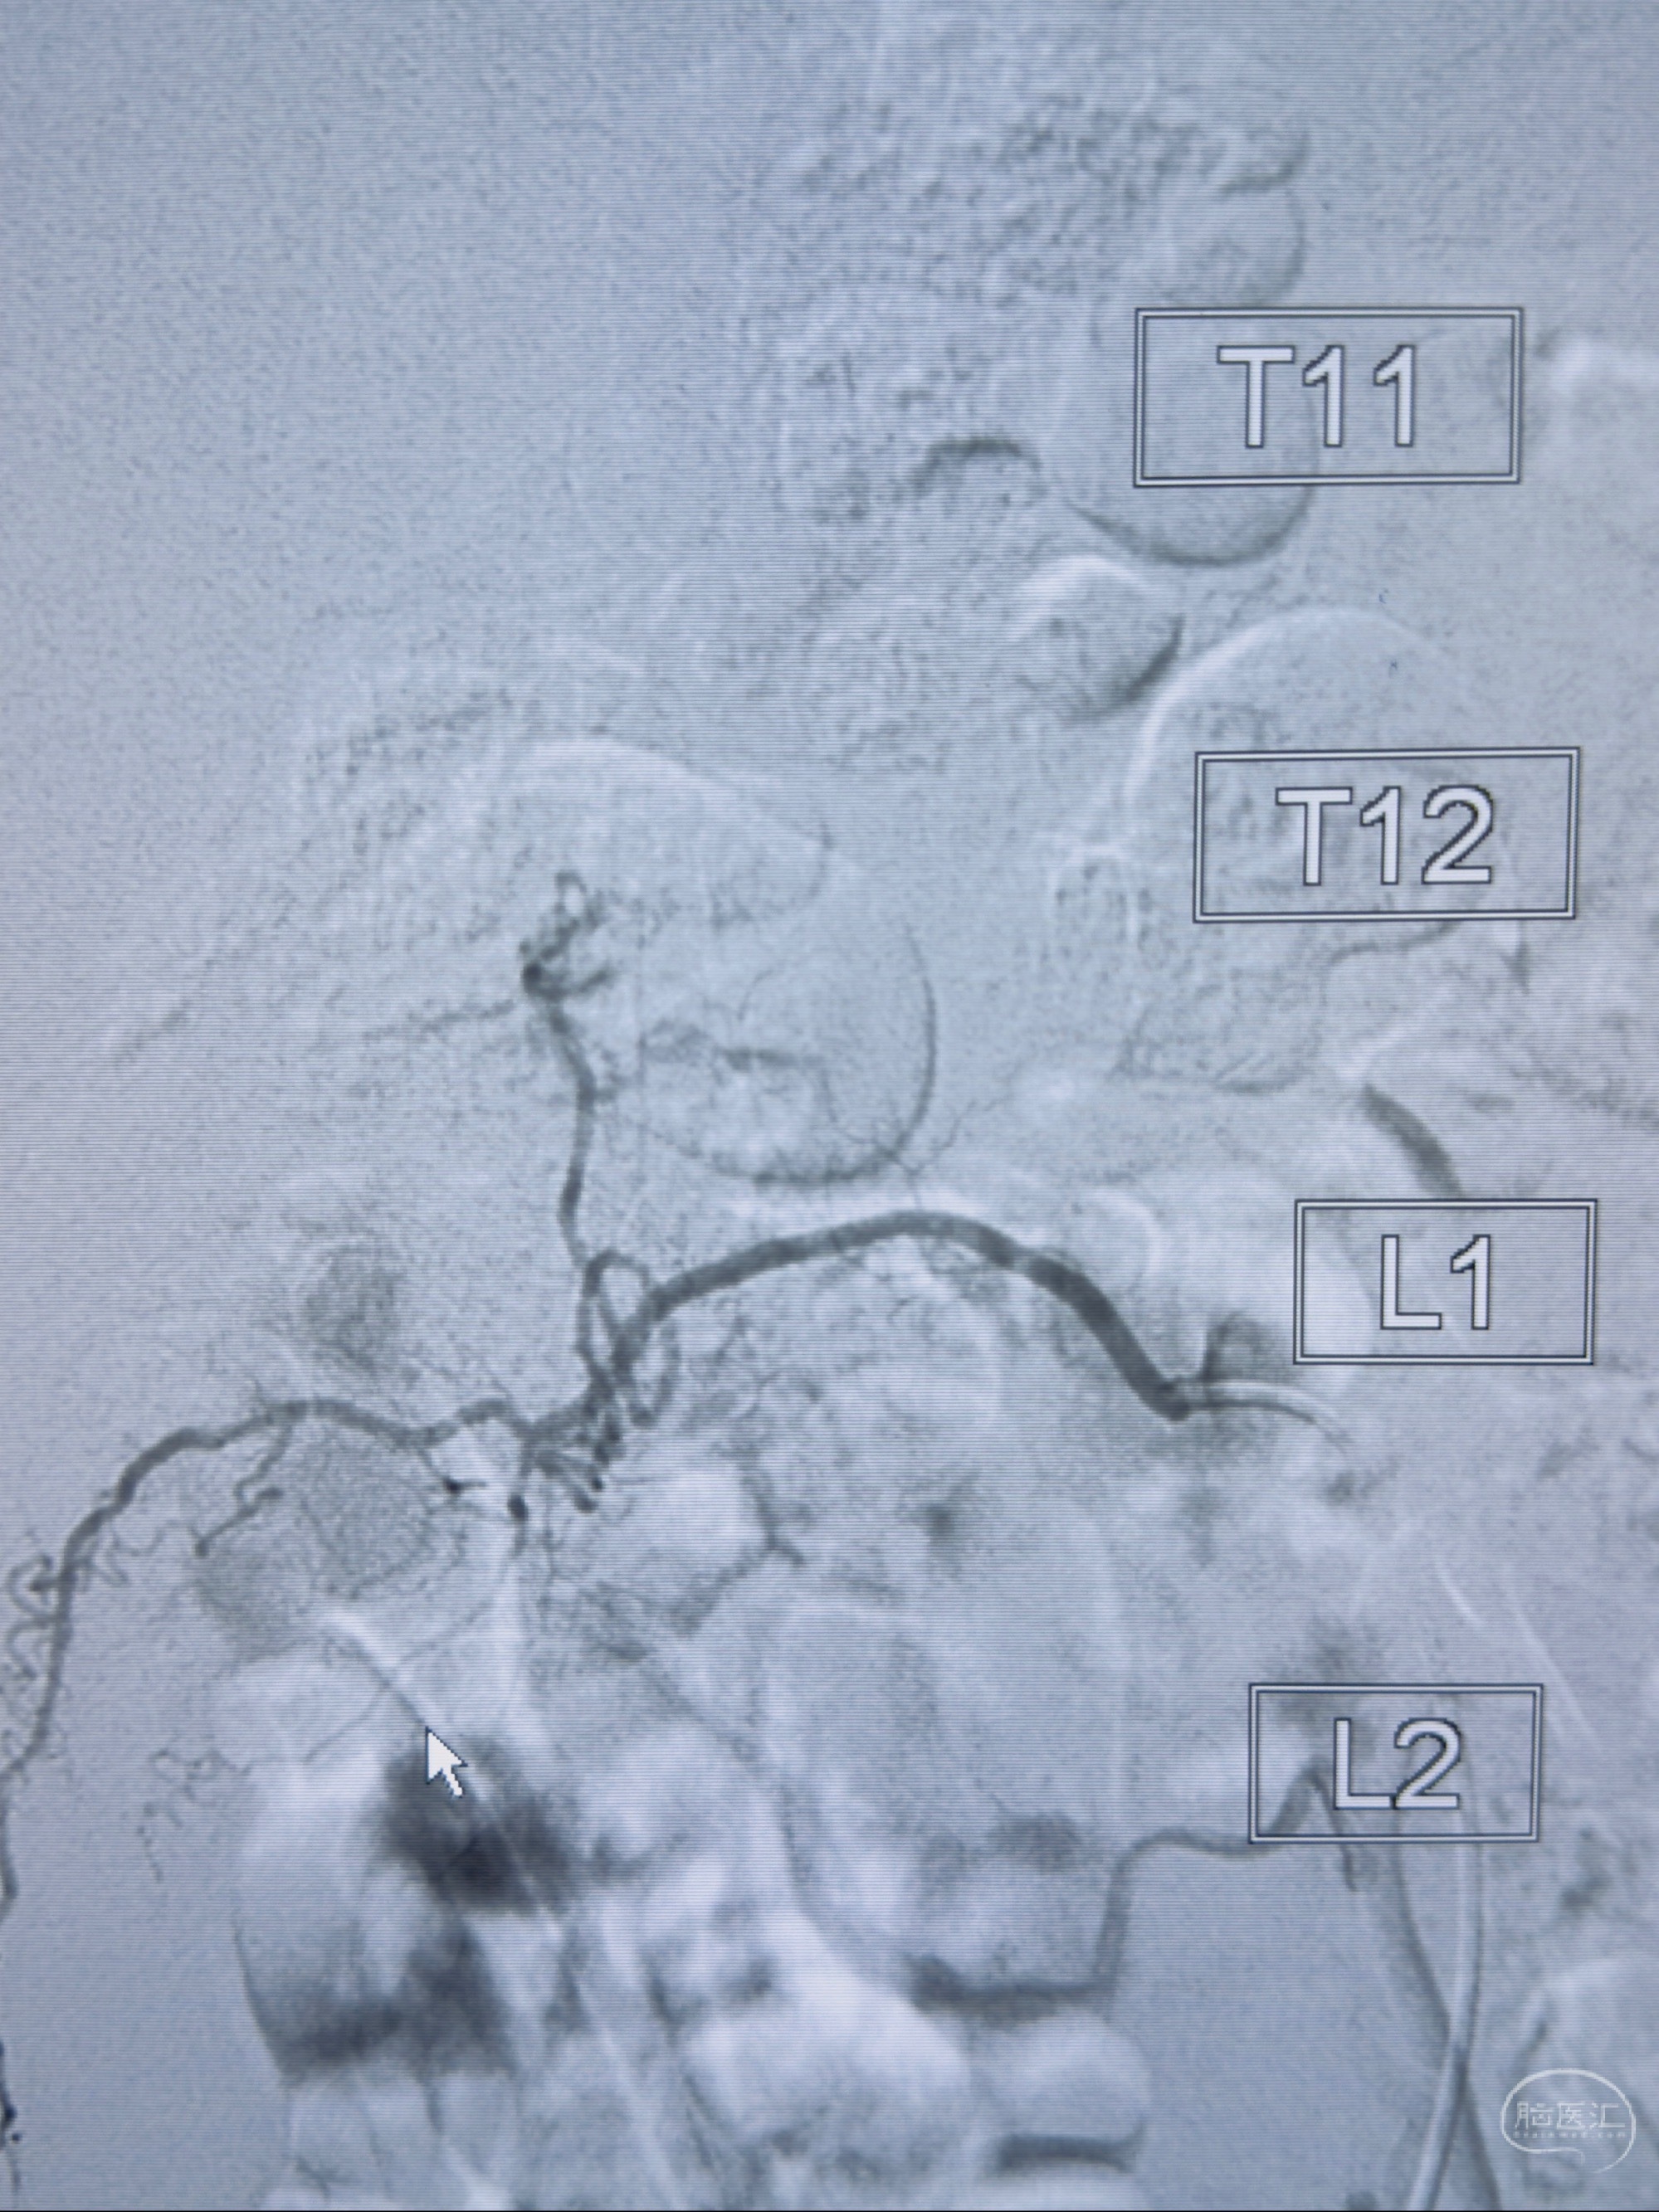

2023-10-13DSA:右侧L1水平硬脊膜动静脉瘘,供血动脉为右侧L1,附近动脉未见明确吻合供血,供血动脉处可见脊髓前动脉发出